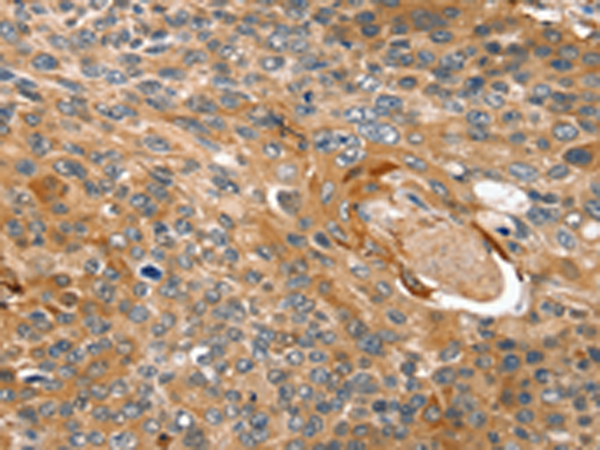

分类: 科研抗体货号: P08790别名: SVAP1; HEL170; SNAP-47; C1orf142; ESFI5812; HEL-S-290应用: IHC反应种属: Human